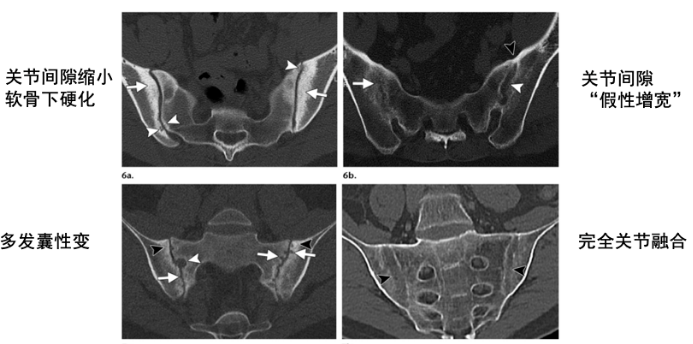

CT:结构变化比X线更灵敏,可更详细地评估骶髂关节病变,较MR可更好地评估关节韧带部分的骨质增生。

结构性破坏(慢性改变)包括软骨下骨硬化,骨质侵蚀,关节周围脂肪沉积,骨桥、关节强直。